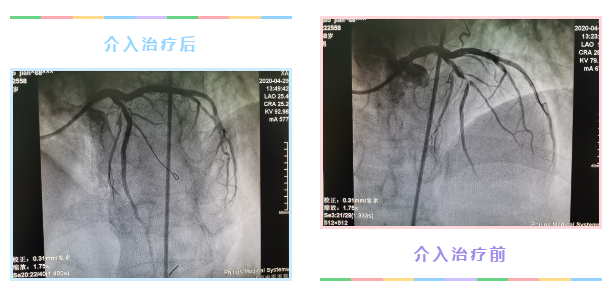

1个多月前,68岁的高大爷突发胸闷、胸痛来我院就诊,心电图提示胸壁导联弓背抬高,心肌酶阳性,诊断为“急性前壁心肌梗死”。胸痛中心立即启动,为高大爷行冠脉造影术,术中发现其前降支血管急性血栓形成,同时右冠状动脉病变也很重。如不能及时开通闭塞血管,高大爷随时会猝死,或发生大面积心肌坏死,导致恶性心力衰竭、恶性心律失常等。时间就是生命,心血管科主任刘红旭和副主任医师周琦立即决定为其实施冠脉介入治疗。

刘主任带领心血管科介入团队展开手术。由于病变在前降支近段,病情较重,术中高大爷血压降低,医生立刻行主动脉球囊反搏术(IABP),一方面增加其冠脉灌注压,增加供血,另一方面降低心脏后负荷,给缺血的心脏减负。经球囊扩张,血栓抽吸,前降支植入支架,高大爷前降支血流逐渐恢复,胸痛明显缓解,术后安返CCU监护室。